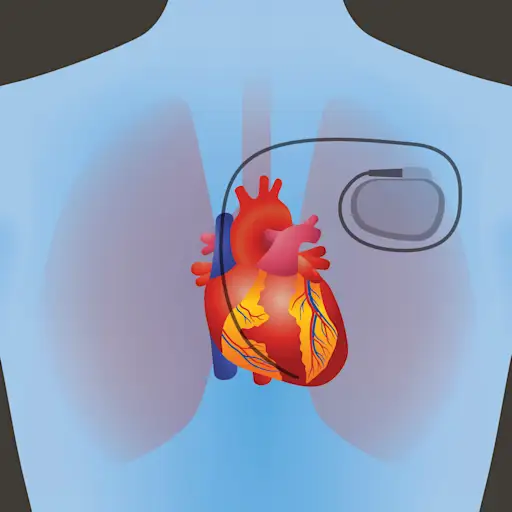

当心肌需要重复,甚至是连续,提醒搏动的顺序,而药物是不够的,不同设备可以帮助。心脏起搏器和植入式心脏复律除颤器(ICDs)这两种设备使医疗专业人员能够根据需要控制病人的心率和泵送能力——准确地在心律失常发生的时候。

设备续。

起搏器可能是临时的或永久性的,内部或外部电池发生器和皮肤下的引线(电线)。这些引线发送电信信息定期收缩心肌。反过来,去纤颤器提供低电击可以重置不规则心跳,大电击可以对抗危险的室性心律失常。与心脏起搏器一样,心脏除颤器使用电池并插入心脏,但该设备被放置在胸部或腹部的皮肤下。

ICD的优点和缺点

对于心脏心律失常损害正常功能并增加死亡率的患者,ICDS是在日常情况和锻炼中提供安心的惊人工具。手术插入设备被认为是微创的,而不是打开胸部。但是,ICDS并非没有风险:它们可以不正确地发挥震动,并且在植入部位可能感染。ICD在一些患者中使用,特别是没有其他心脏病的人,可能很少的死亡效益。